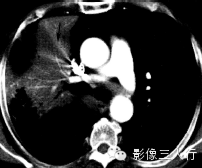

(B)平扫纵隔窗